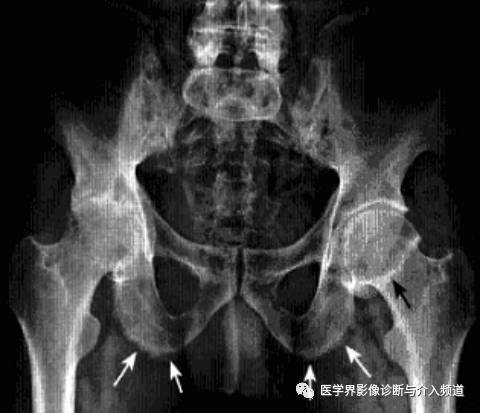

强直性脊柱炎累及髋关节

系累及中轴骨及近端大关节的血清阴性脊柱关节病。病变对称侵及骶髂关节、椎间小关节、附件韧带和近躯干的大关节,最后导致纤维性或骨性强直和畸形。髋关节是本病最常累及的关节,约占50%。

影像诊断:X线片为主要检查手段,MRI能显示早期髋关节改变。

1、平片:双侧对称受累,早期骨质疏松,关节囊膨隆,股骨头及髋臼骨质侵蚀糜烂;中期关节间隙一致性狭窄,软骨下囊性变,关节面边缘骨质增生,坐骨结节、坐骨耻骨支及股骨大转子可伴骨膜炎;晚期股骨头内移、髋臼内突,关节腔闭锁呈骨性强直。

2、CT:早期少量关节腔积液,可伴髂腰肌囊扩张,同时股骨头骨质疏松,股骨头及髋臼缘囊状、虫蚀状骨质缺损;中期关节面边缘硬化、囊变、骨赘形成,股骨头基底滑膜附着处增生,髋关节间隙均匀一致性狭窄消失,双侧髋对称性骨性强直,股骨头及髋臼可普遍性肥大。

3、MRI:①关节积液,关节间隙增宽,②滑膜增厚,增强后明显强化,③关节软骨水肿,④关节面软骨信号改变,炎性血管翳增生,信号强度不均,⑤软骨下囊性变,⑥关节骨性强直。